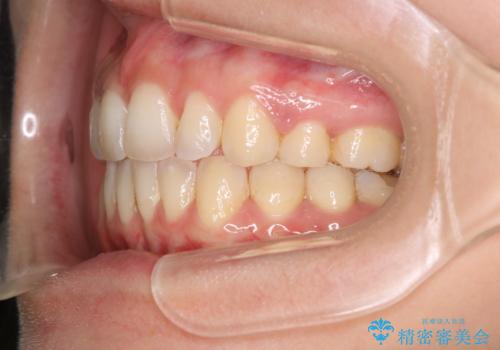

出っ歯で口が閉じずらい ワイヤーによる抜歯矯正

前歯がしっかり下がることで、上下の前歯があわさり食事もしやすくなったと言っていただきました。